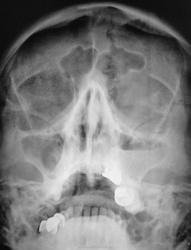

Снижение пневматизазии в проекции ячеек решетчатой кости, горизонтальный уровень в левой в/челюстной пазухе до 2/3 объёма.

пневматизация левой верхне челюстной пазухи снижена за счет пристеночного отека слизистой и выпота...

остальные пазухи воздушные...